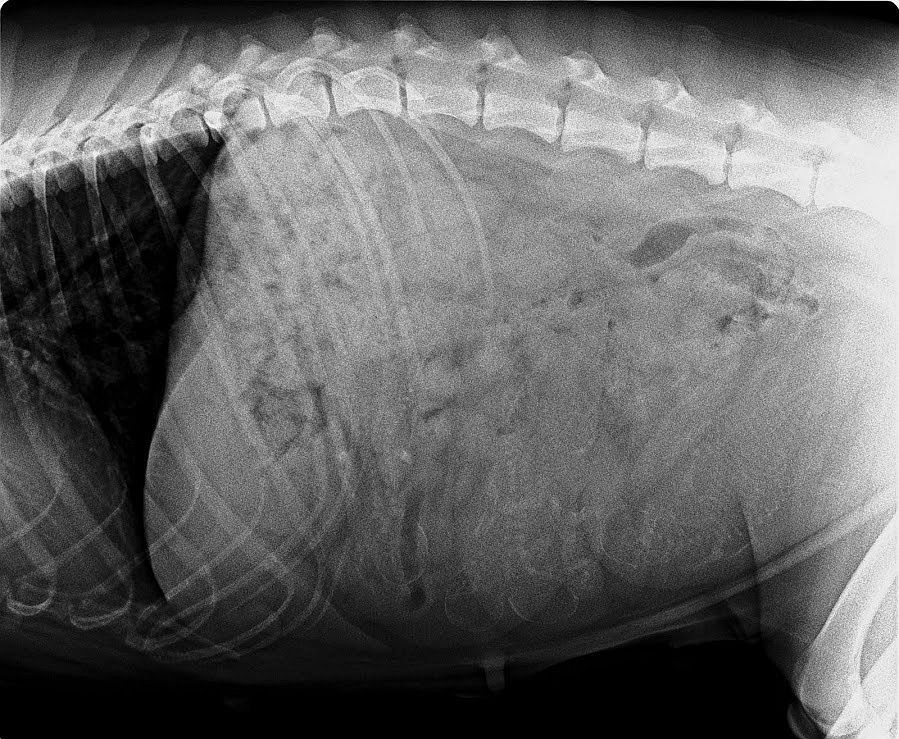

Tag 57

Am 15.4.2020 waren wir beim unserem Tierarzt zum Röntgen. Naja…fangt mal an zu zählen wie viel Babys Hedda in ihrem Bauch hat. Das ist gar nicht so einfach, das Bild ist ein bisschen unklar. Auch der Tierarzt konnte mir nicht die genaue Anzahl der Welpis verraten Hedda macht es echt spannend.

Und Frauchen muss sich in Geduld üben ☺……

Und da wir nun einmal beim Tierarzt waren musste Hedda auf die Waage.

Oh schreck☺…. 31,3 kg und sie hat noch 1 Woche bis die Mäusies geboren werden.

Aber egal…. Hedda geht es sehr gut. Sie ist nach wie vor Mega verschmust und der Hunger ist immer noch unstillbar☺☺☺